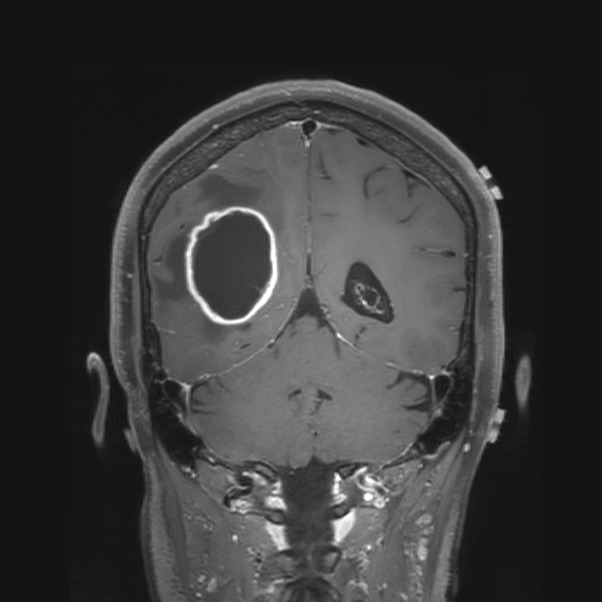

On Tuesday July 22nd, 2025, Sarah Ruffi a beloved Mother, Wife, & Attorney in Wausau, WI was diagnosed with a cancerous brain tumor & given six months to live without surgery.

She was driven to Mayo Clinic in MN where she had a 5 hour brain surgery 2 days later. They were fortunately able to remove most of the tumor but we don't know how long she has, if she's going to make it yet, or if she'll be able to go back to work if she recovers.